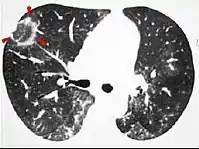

تتكون علامة الهالة المعكوسة من دائرة يتشكل وسطها من عتامة الزجاج المصنفر ويُحيط بها تكثف رئوي يُشكل أكثر من ثلاثة أرباع الدائرة وسماكته 2 مم على الأقل.[4] وهذه العلامة توحي بوجود التهاب القصيبات المسد لذات الرئة المنظم، [5] لكنها لا تظهر إلا في حوالي 20٪ من المصابين، كما يُمكن أن تُشير هذه العلامة إلى احتشاء الرئة (حيث تتكون الهالة بسبب النزف)،[6] أو بعض الأمراض المعدية مثل السل، فطار عفني والرشاشيات، وقد تُشير أيضا إلى فرط الورام الحبيبي والغرناوية. [7]

أشعة مقطعية يظهر فيها علامة الهالة المعكوسة بسبب التهاب القصيبات المسد لذات الرئة المنظم.

أشعة مقطعية يظهر فيها علامة الهالة المعكوسة بسبب احتشاء الرئة (السهم الأسود) نتيجة وجود انصمام رئوي مزمن (السهم الأبيض).